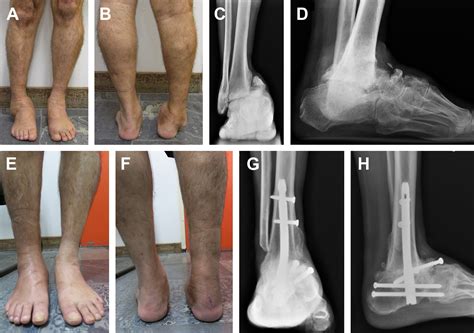

• Correction of severe deformity: To permanently fix the alignment of a joint that has shifted significantly over time.

Ultimately, the goal is to provide stability and pain relief. For many patients, the loss of motion is a minor price to pay for the removal of constant, agonizing pain that previously limited their ability to walk, work, or sleep comfortably.

What to Expect During the Procedure

When you ask your surgeon, "What is arthrodesis from a technical perspective?", they will explain that the surgery involves removing the remaining cartilage from the joint surfaces. Once the raw bone is exposed, the surgeon uses internal hardware—such as metal plates, screws, rods, or pins—to hold the bones in the correct position. Sometimes, a bone graft (either from your own body, a donor, or a synthetic source) is placed between the bones to encourage them to grow together, a process known as osteointegration. Over several months, the body bridges the gap with new bone tissue, completing the fusion.

Living after arthrodesis requires some lifestyle adjustments, but it is important to remember that the body is highly adaptable. While you will lose the range of motion in the fused joint, the surrounding joints often compensate to help you maintain mobility. For example, if you have an ankle fusion, the midfoot joints may experience increased stress, and physical therapy focuses on strengthening the muscles around these areas to maintain balance and gait efficiency.